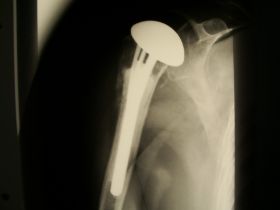

zakres ruchu po endoprotezie stawu ramiennego przy uszkodzeniu stożka rotatorów po urazie z przed 15 lat endoproteza odwrócona (inverse) typu Delta III

endoproteza odwrócona (inverse) typu Delta III : stosowana przy zerwanym stożku rotatorów i artrozie stawu ramiennego